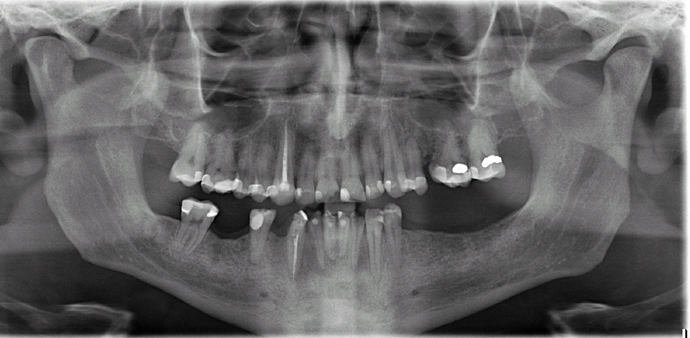

All-on-4/ Full Mouth Dental Implants / Teeth in a Day: Case 18- Upper crowns and Lower All-on-4 Bridge

This patient, a mental health counselor was frustrated that despite taking care of his teeth all his life, he ended up having several cavities that made him lose several of his lower teeth. His cavities in his upper natural teeth was manageable through crowns and his remaining lower teeth were extracted and new implants and teeth were installed in one day without the need for any bone grafting.

Procedures : extractions, implants, All on 4 , Teeth in a day, no bone grafting and full mouth reconstruction with monolithic zirconia bridges.